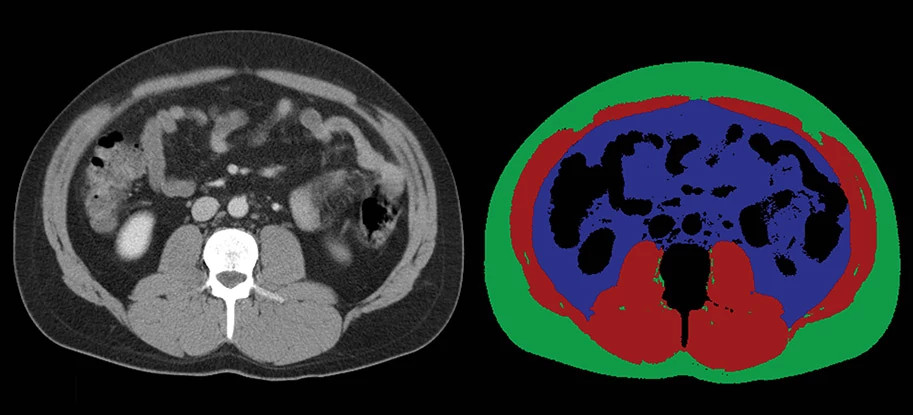

ai-ct-scans-913x415.jpg

AI technology is analyzing CT scans like those pictured here to detect loss of muscle mass, which may be a warning sign of pancreatic cancer.